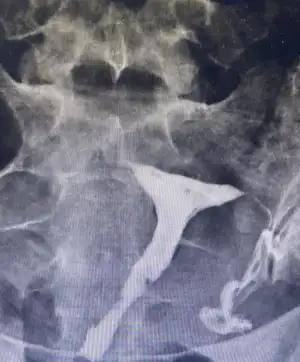

Yakalamışken bn de birşey sorsam olur mu benim sol tüpüm kapalı sağ açık rahim normal fakat bn baktığım zaman sağa doğru çok yatık bu bi sorun oluşturur mu acaba gebelikle alakalı

Bu şekilde canım bişey demedi

Eklentiler

• EB23AD69-EB6C-4BD4-8D81-07F62DB895E4.webp

EB23AD69-EB6C-4BD4-8D81-07F62DB895E4.webp

48,3 KB · Görüntüleme: 37